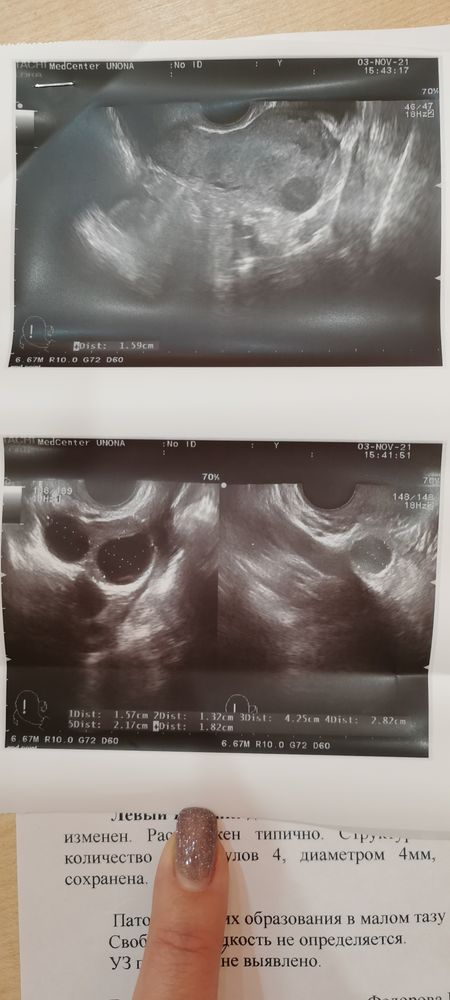

Девочки, в этом месяце у меня первая стимуляция. Вобщем с 2 по 5 дц по 1т клоста. Затем хгч 10.000ед.

Сегодня на 7дц пошла на узи, а там уже есть дом. Фол. 18-22мм. И врач сказала завтра уже делать укол 😱т. Е. На 8 дц цикла. Получается у меня будет такая ранняя овуляция?

Эндометрий конечно ещё мал, цикл то только начался. Сказала дивигель втирать. Подскажите как правильно это нужно делать 🤪...

У меня тоже первая стимуляция - вчера делали узи левый яичник 3 ДФ правый не отреагировал.Сделали ХГЧ укол - с сегодняшего вечера половой акт 4 дня стабильно